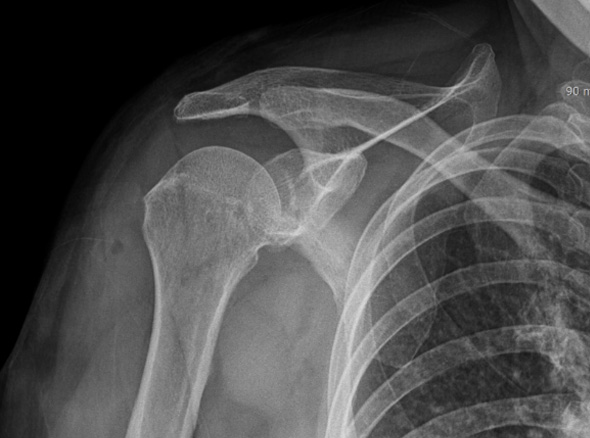

어깨충돌증후군이 발생하게 되면 회전근개에 염증이 발생하게 되고

급성 부종을 일으키게 됩니다.

30대를 시작으로 50대까지 증상이 지속적으로 악화되고 통증도 점차 커집니다.

증상이 심한 경우 일상 생활에 어려움이 발생되어 수술적인 치료를 고려할 수 있습니다.

보존적 치료에 호전되지 않는 경우

회전근개 파열로 진행되고 있는 경우

극심한 통증을 동반하고 있는 경우